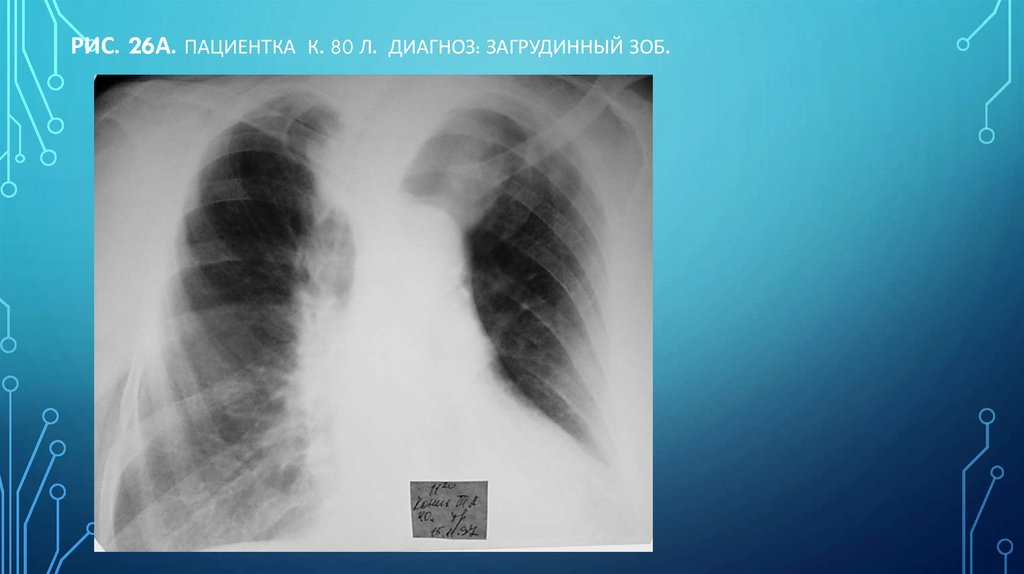

Рис. 26а. Пациентка К. 80 л. Диагноз: загрудинный зоб.

96. Рис. 26а. Пациентка К. 80 л. Диагноз: загрудинный зоб.

Н.С. ВОРОТЫНЦЕВА, С.С. ГОЛЬЕВ РЕНТГЕНОПУЛЬМОНОЛОГИЯ